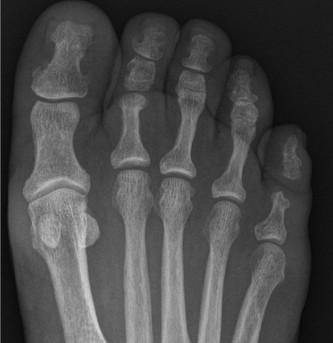

A 54-year-old woman presents to clinic reporting discomfort on the dorsum of her foot with shoewear and pain …

A 60-year-old male presents noting left foot pain of over a year’s duration. He was originally diagnosed with…

A 45-year-old man presents to your office with pain and stiffness in his big toe. He denies any history of tr…